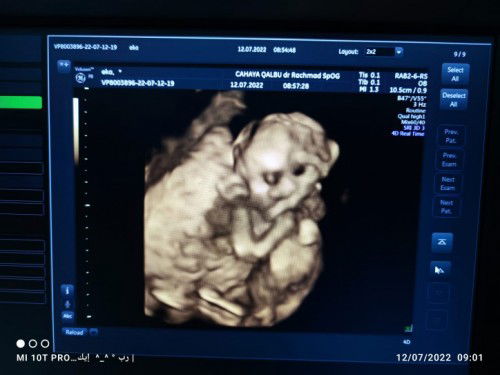

USG 18 MINGGU

Masyaallah usg usia kandungan 18w, selisih 2 minggu lebih cepat dari hpht. Semoga saya dan semua bunda yang sedang hil.Allah berikan kesehatan dan kelancaran Ibu dan bayinya sampai lahiran nanti Aamiin